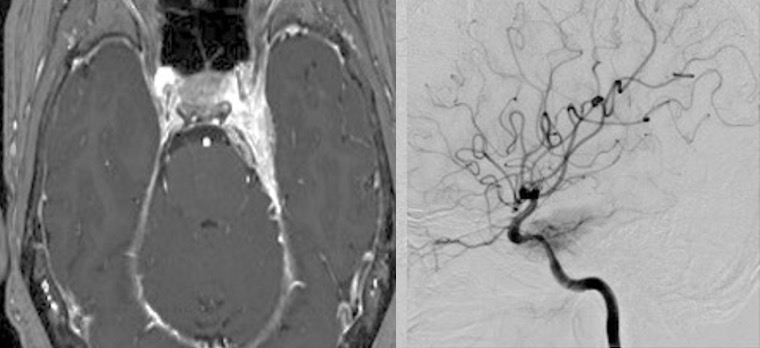

左海綿静脈洞内髄膜腫(複視)に対して、現在のスタンダードは放射線治療になりつつありますが、これも長期制御が困難なので、今回はBTOで左内頸動脈閉塞による血管内腫瘍塞栓を行う計画としました。それに先立ち、BTO時のStump <50mHgであったためSTA-MCAバイパスを行いました。